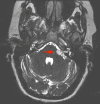

Both lipomas and dermoid cysts of the cerebellopontine angle are rare tumors. These tumors differ in their embryological origin but share similar features on imaging. Both of these congenital lesions can be found in the cerebellopontine angle (CPA), and symptomatic clinical presentation is dictated by the location of the lesion. This paper demonstrates a unique case in which a CPA lipoma was misidentified as a dermoid cyst, leading to surgical intervention. Further, the paper provides a literature review of CPA lipomas and dermoid cysts to aid readers in further differentiating between these two unique tumors.